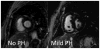

Pulmonary hypertension is a condition of varied etiology, commonly associated with poor clinical outcome. Patients are categorized on the basis of pathophysiological, clinical, radiologic, and therapeutic similarities. Pulmonary arterial hypertension (PAH) is often diagnosed late in its disease course, with outcome dependent on etiology, disease severity, and response to treatment. Recent advances in quantitative magnetic resonance imaging (MRI) allow for better initial characterization and measurement of the morphologic and flow-related changes that accompany the response of the heart-lung axis to prolonged elevation of pulmonary arterial pressure and resistance and provide a reproducible, comprehensive, and noninvasive means of assessing the course of the disease and response to treatment. Typical features of PAH occur primarily as a result of increased pulmonary vascular resistance and the resultant increased right ventricular (RV) afterload. Several MRI-derived diagnostic markers have emerged, such as ventricular mass index, interventricular septal configuration, and average pulmonary artery velocity, with diagnostic accuracy similar to that of Doppler echocardiography. Furthermore, prognostic markers have been identified with independent predictive value for identification of treatment failure. Such markers include large RV end-diastolic volume index, low left ventricular end-diastolic volume index, low RV ejection fraction, and relative area change of the pulmonary trunk. MRI is ideally suited for longitudinal follow-up of patients with PAH because of its noninvasive nature and high reproducibility and is advantageous over other biomarkers in the study of PAH because of its sensitivity to change in morphologic, functional, and flow-related parameters. Further study on the role of MRI image based biomarkers in the clinical environment is warranted.